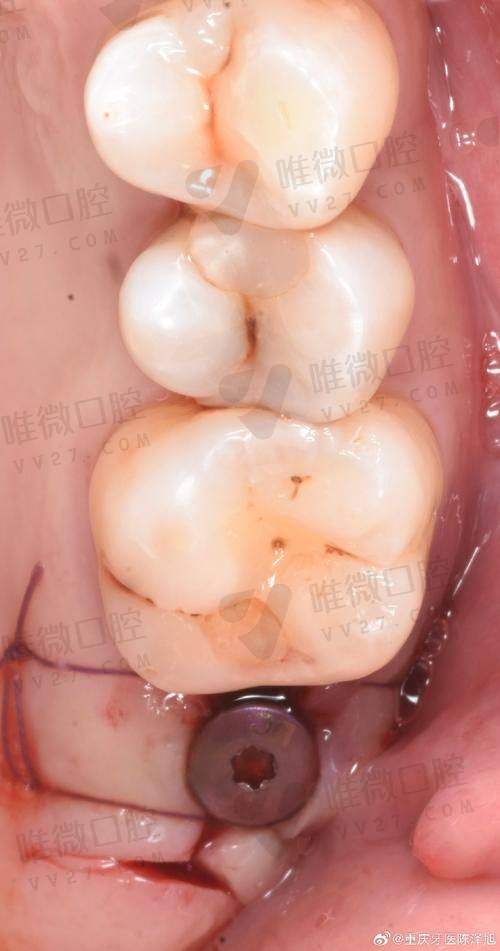

医疗设备角度分析,牙博士的数字示范系统非常炫目,运用3D口内扫描、口腔数据实时投影等技术,可达到即刻建模、建牙的体验感。特别是在做3D打印种植牙时,完成时间快、创伤更小。而可恩则更注重“操作稳扎稳打”,虽然没有酷炫投屏,但其种植导航系统、牙周治疗仪这些设备也是市面上主流高配,适合追求稳定安心治疗者。